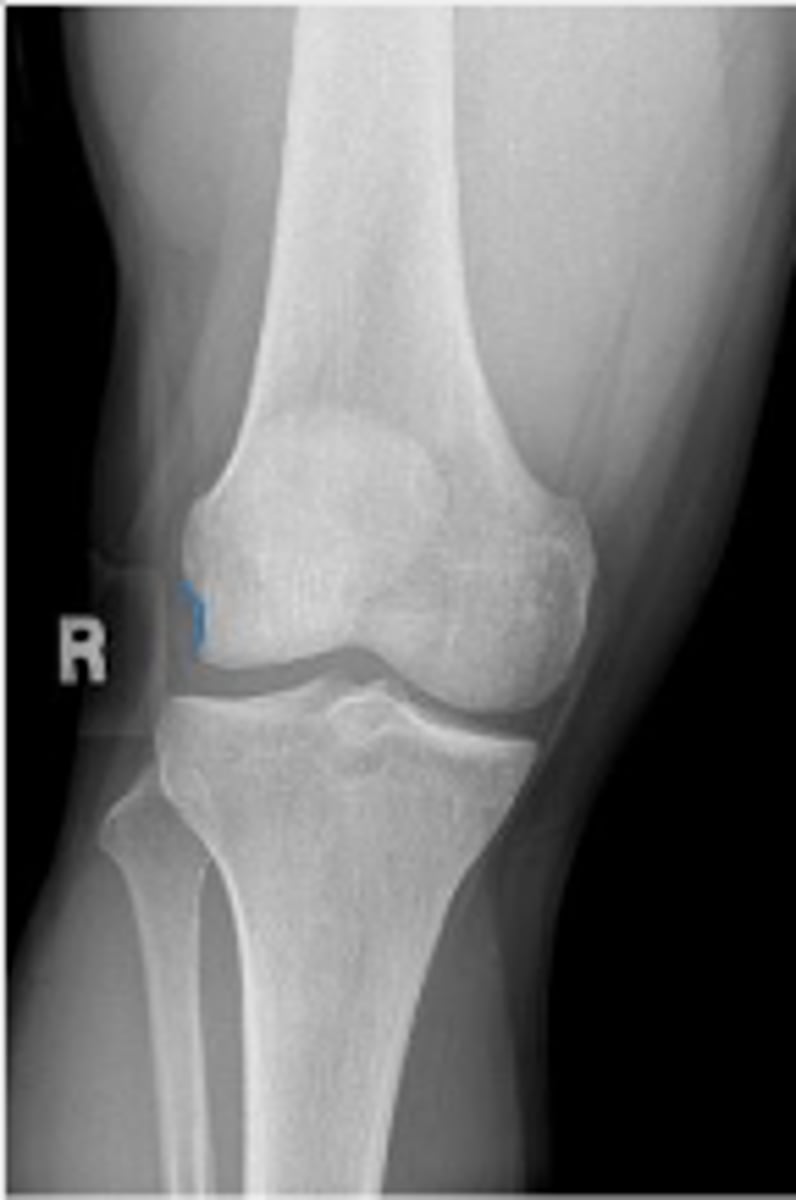

Right AP knee

What is the name of the radiographic view?